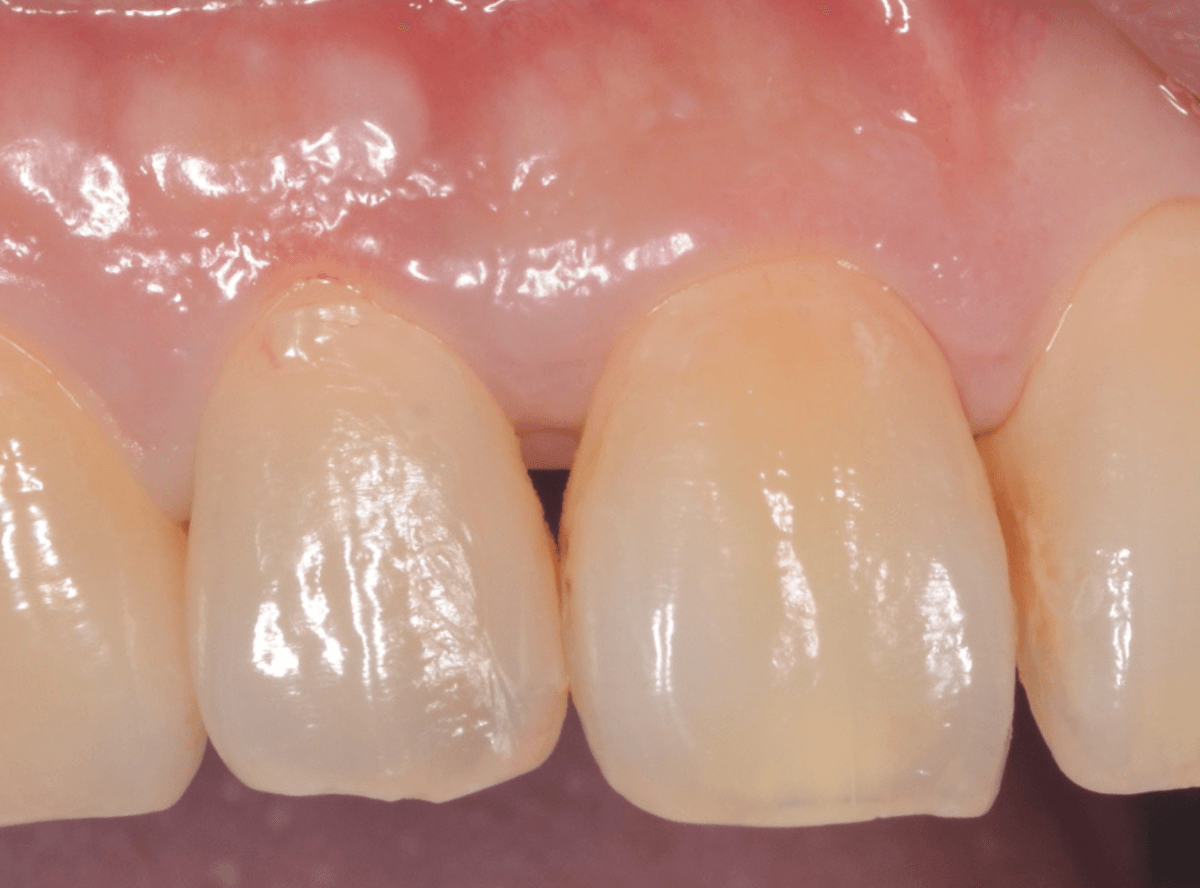

歯石除去後、約1週間です。

歯肉がひきしまってきたのがわかるでしょうか。

治療前との比較です。

比べると、違いがわかると思います。

まだ若い患者さんで本格的な歯周病に進行する前ですので、歯ブラシの徹底によって、もっと歯肉が改善されるのも期待できます。